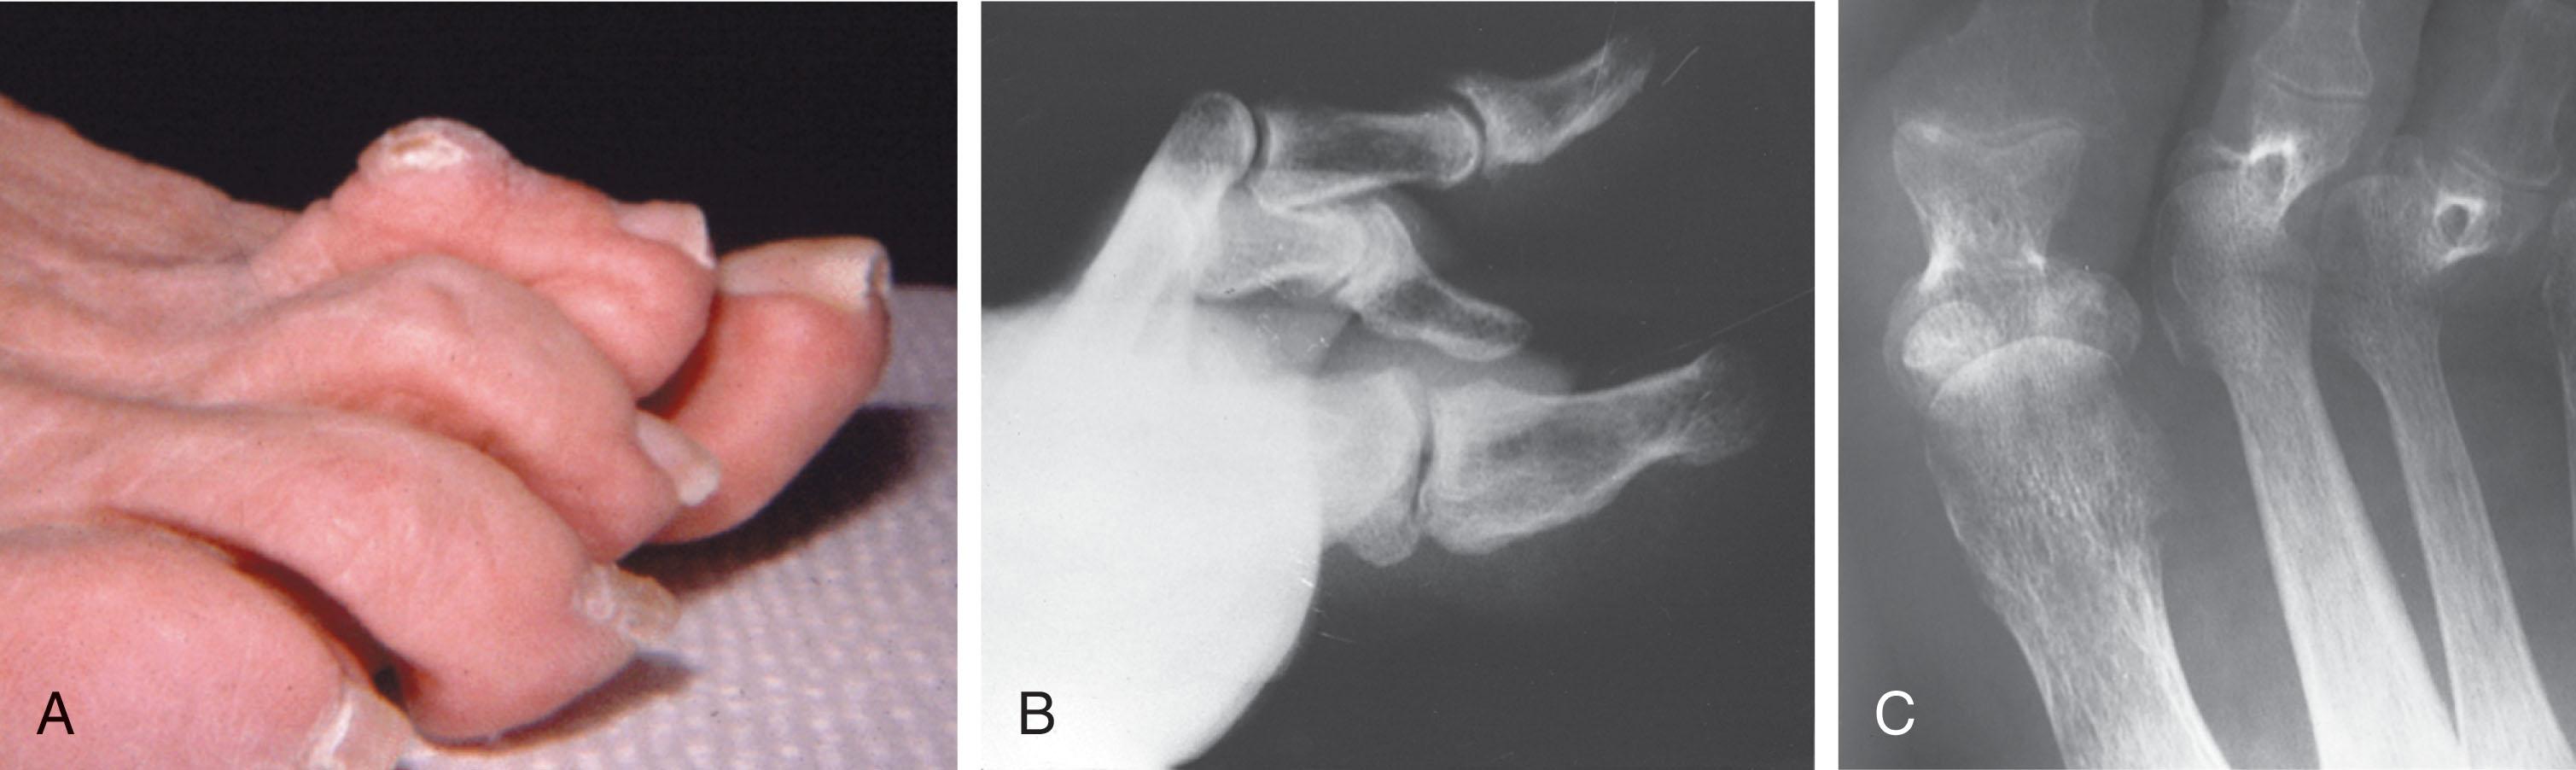

Claw Toe

A claw toe is a result of muscle imbalance between the intrinsic and extrinsic musculature. Simultaneous contracture of the long flexors and extensors of the toe, without the modifying action of the intrinsic muscles of the foot, causes the typical deformity seen in this condition ( Figs. 9-21 and 9-22 ). Taylor, however, found no abnormality of the intrinsic muscles in a series of 68 patients who had claw toes and in whom the muscles were examined by gross inspection, stimulation, and histologic analysis.

A claw toe deformity usually involves multiple toes and often both feet ( Figs. 9-24 and 9-25 ). The deformity may be either rigid or flexible. It is often associated with a cavus foot, with or without a contracted Achilles tendon. Claw toes are often made worse because the patient cannot find adequate shoes, and a painful bursa develops over the PIP joint. As the claw toe deformity becomes more rigid, the toes strike the top of the shoe, and the metatarsal heads are forced plantarward. As the toes subluxate dorsally, the plantar fat pad is pulled distally, and the metatarsal heads become more prominent on the plantar aspect of the foot. This deformity can result in the development of painful plantar callosities, which can ulcerate in severe cases, particularly if sensation of the foot is impaired.